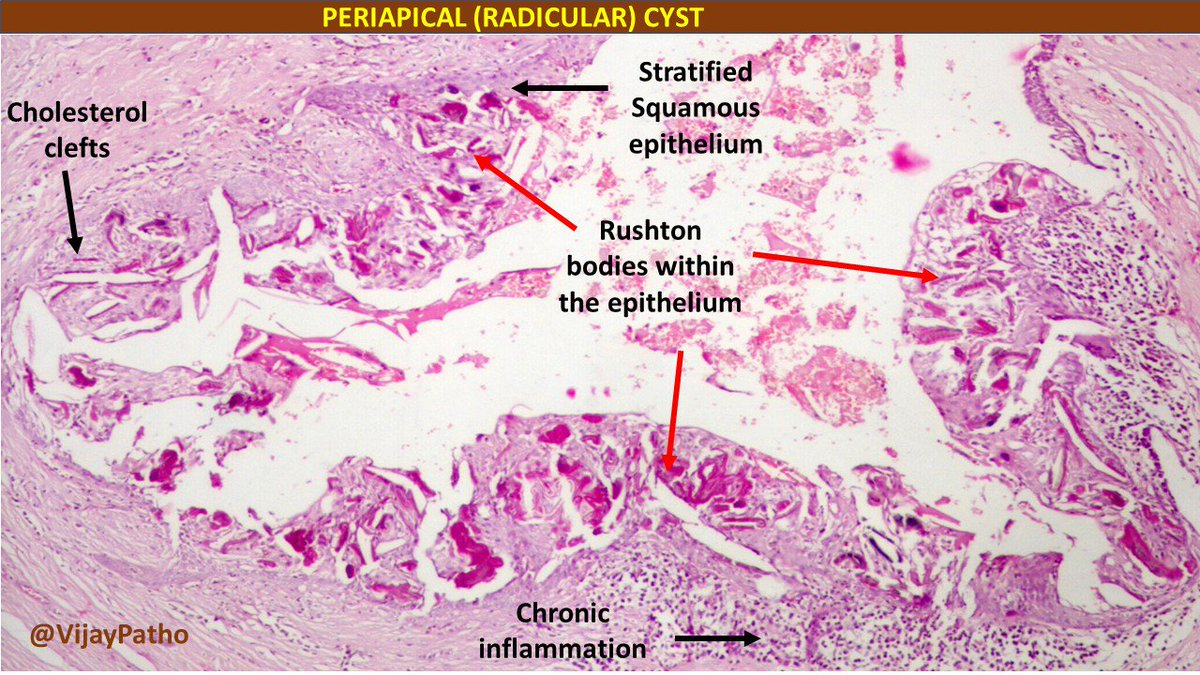

- cholesterol clefts

- 齒源 → Rushton bodies

| Periapical(radicular) cysts | Rest of Malassez 被刺激 | - | - | true/ periapical cyst 圓形的光通性包圍根尖 |

牙根吸收, 2cm ↑ 根管治療無效  |

- Rest of Malassez

- Hertwig’s epithelial 殘留

- Rushton bodies

- 齒源系上皮